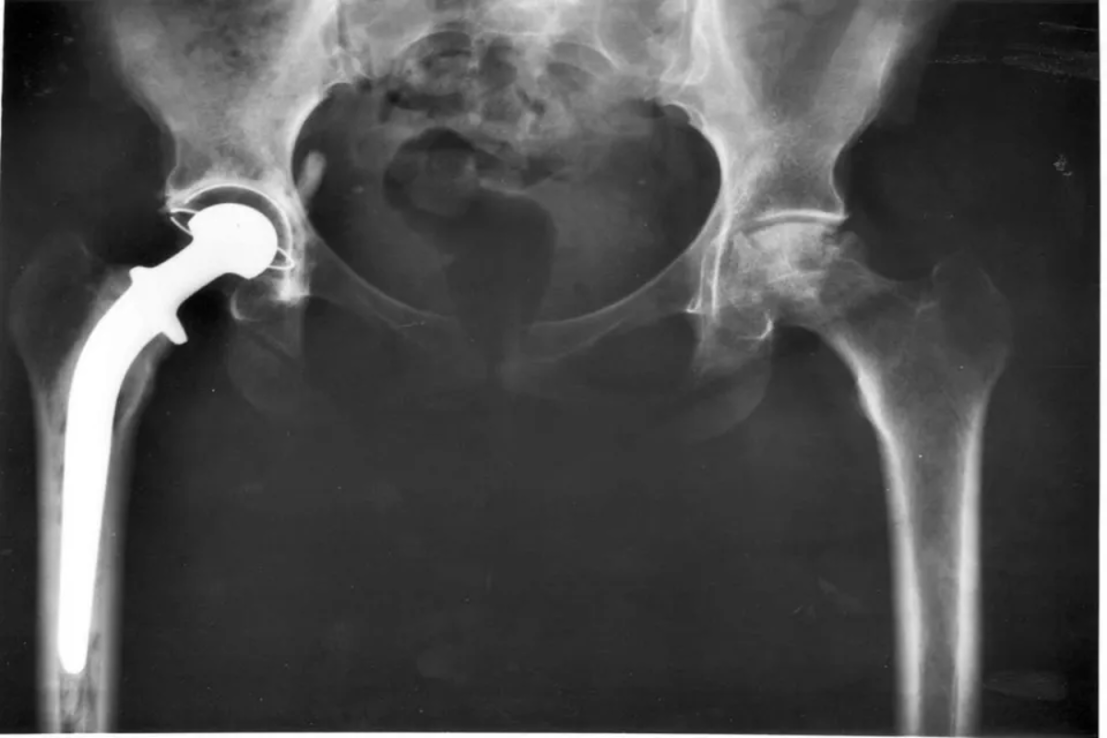

Smith & Newphew is one of the world’s largest hip replacement manufacturers.

The division, which makes replacement hip and knee joints, is the company’s largest but also the slowest-growing compared to its other business lines of wound management and sports medicine.